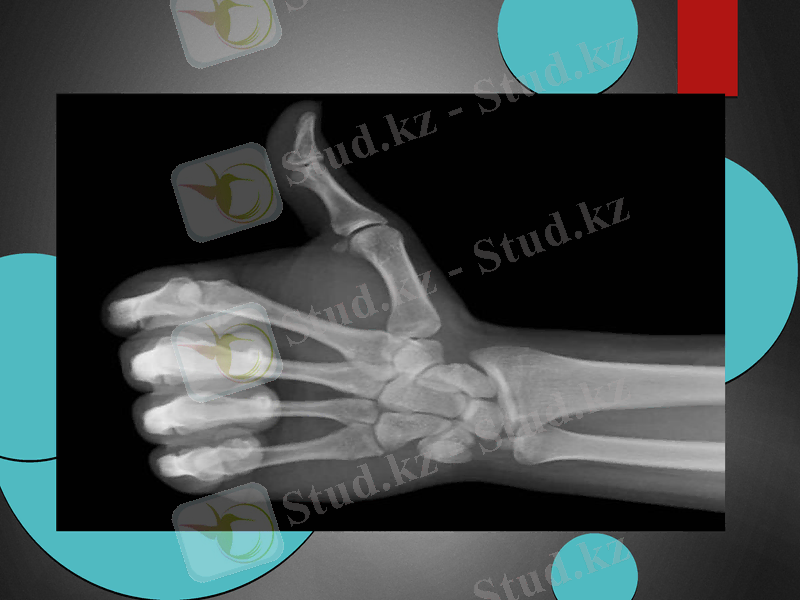

Рентген сәулесі

Рентген сәулесі - гамма және ультракүлгін сәулелер арасындағы диапазонды қамтитын электрмагниттік толқындар. Толқын ұз. 2 ангстремнен кіші Рентген сәулесі шартты түрде қатаң, 2 ангстремнен үлкен Рентген сәулесі жұмсақ Рентген сәулесі деп аталады. Рентген сәулесін 1895 ж. неміс физигі В. К. Рентген ашқан. Ол 1895 - 97 ж. Рентген сәулесінің қасиеттерін зерттей отырып, алғашқы рентген түтігін жасады. 1912 ж. Рентген сәулесінің дифракциясы ашылып, кристалдардың құрылымы периодты болатыны дәлелденді. 20 ғ-дың 20-жылдары рентгендік спектрлер материалдарға элементтік талдау жасауға, 30-жылдары заттың электрондық энергетик. құрылымын зерттеуге қолданыла бастады.

Рентген сәулесі түзілу механизміне байланысты үздіксіз және сызықтық болады.

Үздіксіз Рентген сәулесі зарядталған шапшаң бөлшектердің (мыс., катодтан ұшып шыққан электрондар) нысана атомдарының сыртқы электрондық қабаттармен әсерлесуі нәтижесінде пайда болады

Сызықтық Рентген сәулесі - ішкі электрондық қабаттармен әсерлесуі нәтижесінде пайда болады.

Рентген сәулесінің затпен әсерлесуі кезінде Рентген сәулесі жұтылады, шашырайды немесе фотоэффект құбылысы байқалады.